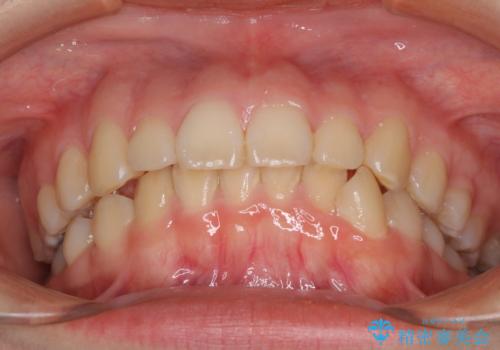

- 口元の突出感を気にして来院された患者様です。

上下左右の第一小臼歯4本を抜歯して口元を下げる治療計画としました。

目立たない装置が希望であったため、上顎が裏側装置である、ハーフリンガル装置を選択されました。

非常に大きな虫歯のあった下顎大臼歯は、根管治療を行い、矯正治療後にオールセラミッククラウンにて補綴治療を行いました。

当初予定では3年以上かかるとお伝えしておりましたが、スムーズに歯列が整い、2年強で終了することができました。